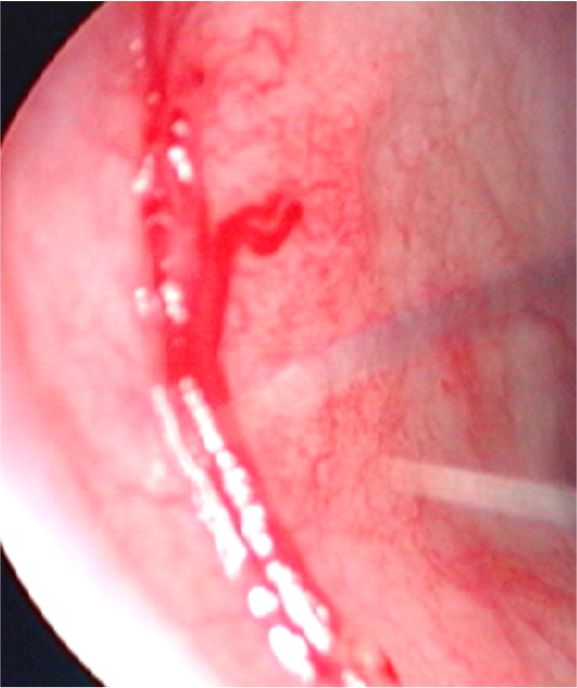

・出血部位が明らかで、鼻の入り口近くのものは電気メスで痛んだ血管を凝固して止血します。